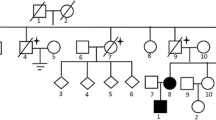

A total of 39 patients (37 Females, 2 Males) from 31 distinct families were diagnosed with BHDS by genetic testing (Table 1). The average age at diagnosis was 45.8 years (median = 48 y, range: 15–72 y, with one case unknown). Based on all information available, 85.7% (24/28) BHDS patients have a family history of lung cysts and/or spontaneous pneumothorax, and 2 (7.1%, 2/28) patients have a family history of renal tumor. In our cohort, 3 patients failed to follow-up, and all the rest 36 (100%, 36/36) patients have lung cysts (Fig. 1a), and 21 (58.3%, 21/36) have a history of pneumothorax. Seventeen (47.2%, 17/36) patients got cutaneous lesions (Fig. 1b) with multiple white or skin colored papules on the face, neck and/or feet. Renal impairment was observed in 9 (30%, 9/30) patients, including 8 with unilateral or bilateral renal cysts (Fig. 1c) and 1 with renal hamartoma. No malignant renal tumor was found in this cohort.

Mutation screening by direct sequencing and MLPA analysis of the FLCN gene were performed in a total of 39 unrelated probands. Out of them, each of 31 probands was confirmed to carry a suspected disease-causing variant in FLCN (Table 1). The overall variant detection rate was therefore 79.5% (31/39). Altogether, 24 distinct variants were identified, including 21 (87.5%, 21/24) truncating variants (including nonsense, frameshift, putative splicing mutation and gross deletion) predicted to cause complete loss of function of folliculin, 2 in-frame small deletions and 1 synonymous variant. The mutational hot spot, a single duplication/deletion of cytosine in exon 11, was observed in 8 probands (6 c.1285dupC and 2 c.1285delC), which was the most frequent mutation in our cohort. Interestingly, a new form in this poly-cytosine tract, c.1283insG, was found in proband 2–1 and her affected daughter.

Among the 24 germline variants detected in this study, 14 (58.3%, 14/24) were found to be novel variants. According to the ACMG/AMP 2015 guidelines [14], 11 novel variants were classified as pathogenic (Ia – Ic), including 5 frameshift, 2 nonsense, 3 canonical splice site variants and 1 gross deletion. The gross deletion at FLCN exon 1 (△Exon 1) was detected in proband 22 by MLPA and validated by genome DNA qPCR (Fig. 2a, b). Characterization of the breakpoints using long-range PCR showed that there was a deletion of 3.6 Kb encompassing the entire exon 1 (Fig. 2c). The gross deletion was flanked by a repeat element AluSx in intron 1 and an AluSq in the upstream region of FLCN.

Variant c.249 + 1G > A was found in proband 9–1 and her affected mother 9–2 (Fig. 3a), which was predicted to disrupt the canonical splice site. RT-PCR analysis of the mRNA from peripheral blood of the patient was performed. In the absence of the normal splice site, a cryptic splice site within exon 4 was adopted during mRNA splicing process, resulting in an aberrant transcript bearing a partial deletion of 125 bp in FLCN exon 4 (Fig. 3b). The resultant out-of-frame deletion in exon 4 led to a premature termination codon.

In our previous study, 14 out of 20 variants found in a Chinese BHDS cohort were novel [7], indicating a different mutation spectrum from that of Caucasians. And in the present study, as a follow-up study, more than half (52.4%, 11/21) of the 21 detected different variants have never been reported. Collectively, these two studies demonstrated the variability of FLCN mutation spectrum between Chinese and other races. A previously reported mutational hot spot, c.1285dupC/delC, is also the most frequent mutation observed in these two studies, with a frequency (28.3%, 15/53) comparable to that of Japanese patients (28.3%, 34/120) [6]. However, the other two mutational hot spots c.1347_1353dupCCACCCT (p.Val452ProfsX6) and c.1533_1536delGATG (p.Trp511X) reported in Japanese were not observed in our cohort. The only one mutation observed in more than 5 patients is c.1285dupC. We compared the pulmonary, cutaneous and renal manifestations between c.1285dupC carriers and other patients. No association was observed between this mutation with any clinical features in our cohort.

Gross intragenic rearrangements of FLCN were less frequently reported. To our knowledge, the Exon 1 deletion identified in this study is the second gross deletion reported in Chinese BHDS patients. Unlike the first reported △Exon 8 mutation [7], this deletion is located in the 5′-untranslated region. Long-range PCR and bidirectional sequencing revealed a 3.6 Kb deletion encompassing the entire exon 1 flanked by the repeat elements AluSx in intron 1 and AluSq in the upstream region of FLCN. Benhammou et al. [21] reported several BHDS families carrying deletions involving exon 1 and found that the genomic sequences of this region contain a significantly higher number of Alu elements than the rest of the entire FLCN gene, which in turn might be responsible for the deletions due to unequal crossover mediated by these Alu elements. In vitro luciferase reporter assay indicated that this region contains the putative FLCN promoter [21], deletion of which will significantly reduce the expression of FLCN, supporting the pathogenicity of this △Exon 1 mutation.